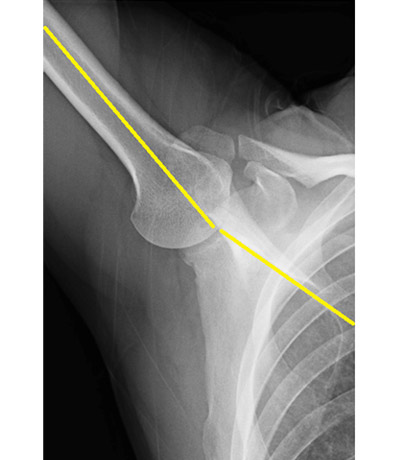

10代男児(野球の投球にて右肩の痛み)

※上腕骨の回旋ストレスを無くす特殊な姿勢で撮影

正常

上腕骨と肩甲骨の肩甲棘がバランスよく一致